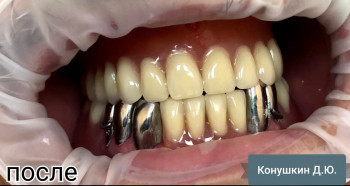

Конушкин Данил Юрьевич: портфолио (1)